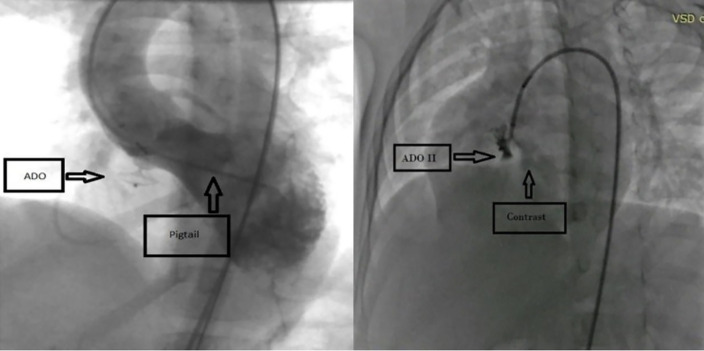

Background: Percutaneous closure of perimembranous ventricular septal defects (pmVSD) with Amplatzer duct occluder type II (ADO II) is a novel method. The present study aimed to evaluate the short and mid-term outcomes of this method in children and adolescents.

Conclusion: Overall, ADO II appeared to be a safe transcatheter occlusion device for patients with pmVSD, and this method could reduce the severity of TR, MR, and AR with few complications.